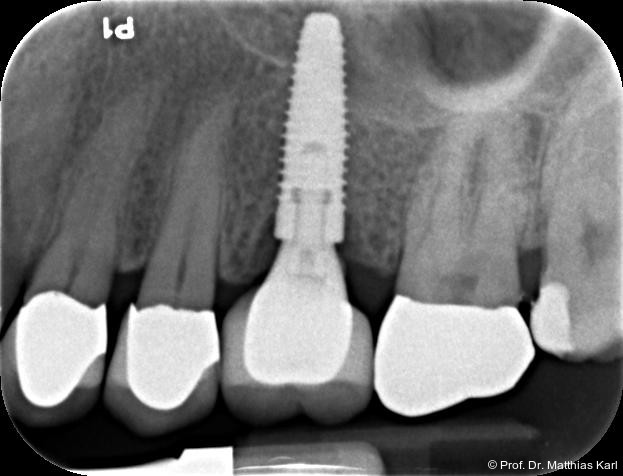

Mikrobewegungen im Verhältnis zum umgebenden Knochenlager. Die Vermeidung solcher Bewegungen ist essenziell, um eine erfolgreiche Osseointegration und damit die Entwicklung einer sekundären, biologisch bedingten Stabilität zu ermöglichen.18 Zur Verkürzung der Behandlungsdauer und zur Ermöglichung einer frühzeitigen prothetischen Versorgung wurden die klassischen operativen Protokolle angepasst. Hierzu zählen die untermaßige Implantatbettpräparation7 sowie der Einsatz konischer Implantatkörper21 (Abb. 1a–2b) mit ausgeprägt aggressiver Gewindegeometrie.8, 14 Beide Maßnahmen führen zu einer erhöhten Kompression des Alveolarknochens, insbesondere in den kortikalen Anteilen.11, 22

Ein wesentlicher Parameter für den Erhalt der Funktion und Ästhetik zahnärztlicher Implantate ist der Zustand des periimplantären Knochens,17 weshalb dessen Niveau relativ zur Implantatschulter kontinuierlich röntgenologisch überwacht wird. Der periimplantäre Knochenverlust gilt nach wie vor als entscheidendes Erfolgskriterium. Grenzwerte für den Knochenverlust sind dabei auf 1 mm im ersten Jahr nach der Implantation festgelegt, gefolgt von maximal 0,2 mm jährlich in den folgenden Jahren.2, 6, 19

Zur Reduktion der Knochenkompression, insbesondere der bukkal gelegenen Lamelle (Abb. 3), werden derzeit Implantate mit dreieckigem Querschnitt10, 12 sowie Implantate mit zervikal reduziertem Durchmesser16 angeboten. Diese scheinen jedoch im Gegensatz zur subkrestalen Positionierung (Abb. 4a–c) von Implantaten23 keine signifikanten Vorteile zu bieten. Bohrprotokolle, welche sowohl auf das jeweilige Implantatsystem als auch auf die vorliegende Knochenqualität abgestimmt sind, haben ebenfalls das Ziel, zu hohe Einbringdrehmomente zu vermeiden.